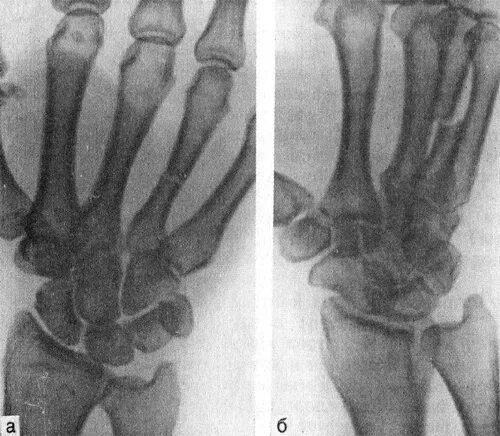

Перелом 3 пястной кости